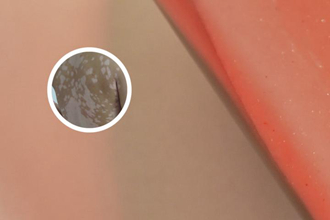

白點(diǎn)癲在皮膚鏡下呈現(xiàn)為白色斑點(diǎn)狀或小片狀的色素缺失區(qū)域。這些缺失區(qū)域一般較小且零散分布,形狀不規(guī)則,經(jīng)常無規(guī)律地散在皮膚各處。白點(diǎn)癲周圍的正常皮膚可能出現(xiàn)輕度紅斑或色素沉著,形成對比。

皮膚鏡下觀察還可以看到白點(diǎn)癲病變區(qū)域的毛細(xì)血管改變,通常表現(xiàn)為毛細(xì)血管網(wǎng)的擴(kuò)張和充血。這種改變反映了白點(diǎn)癲病變區(qū)域血流的異常,可能與色素沉積和色素缺失有關(guān)。

在皮膚鏡下觀察,白點(diǎn)癲的斑塊通常會出現(xiàn)表皮層的變化。由于色素細(xì)胞的損害,斑塊區(qū)域的表皮層會呈現(xiàn)出顯然的色素減少或消失現(xiàn)象。同時(shí),表皮層也可能出現(xiàn)角化不良或過度角化的現(xiàn)象,使得斑塊區(qū)域與周圍皮膚表面有所不同。

色素細(xì)胞是控制皮膚顏色的主要細(xì)胞,對白點(diǎn)癲的觀察中十分重要。在皮膚鏡下,可以看到斑塊區(qū)域的色素細(xì)胞數(shù)量減少或盡量喪失。一些文獻(xiàn)還提到,在白點(diǎn)癲的斑塊中,部分色素細(xì)胞可能會發(fā)生退化,變得異常扁平或不規(guī)則形狀。

白癜風(fēng)斑塊的發(fā)展與血管系統(tǒng)也存在一定的關(guān)聯(lián)。調(diào)查發(fā)現(xiàn),白點(diǎn)癲的斑塊區(qū)域血管密度增加,血管形態(tài)也可能發(fā)生改變。這些改變導(dǎo)致斑塊周圍的微循環(huán)異常,進(jìn)一步影響到局部的營養(yǎng)供應(yīng)和色素沉著。